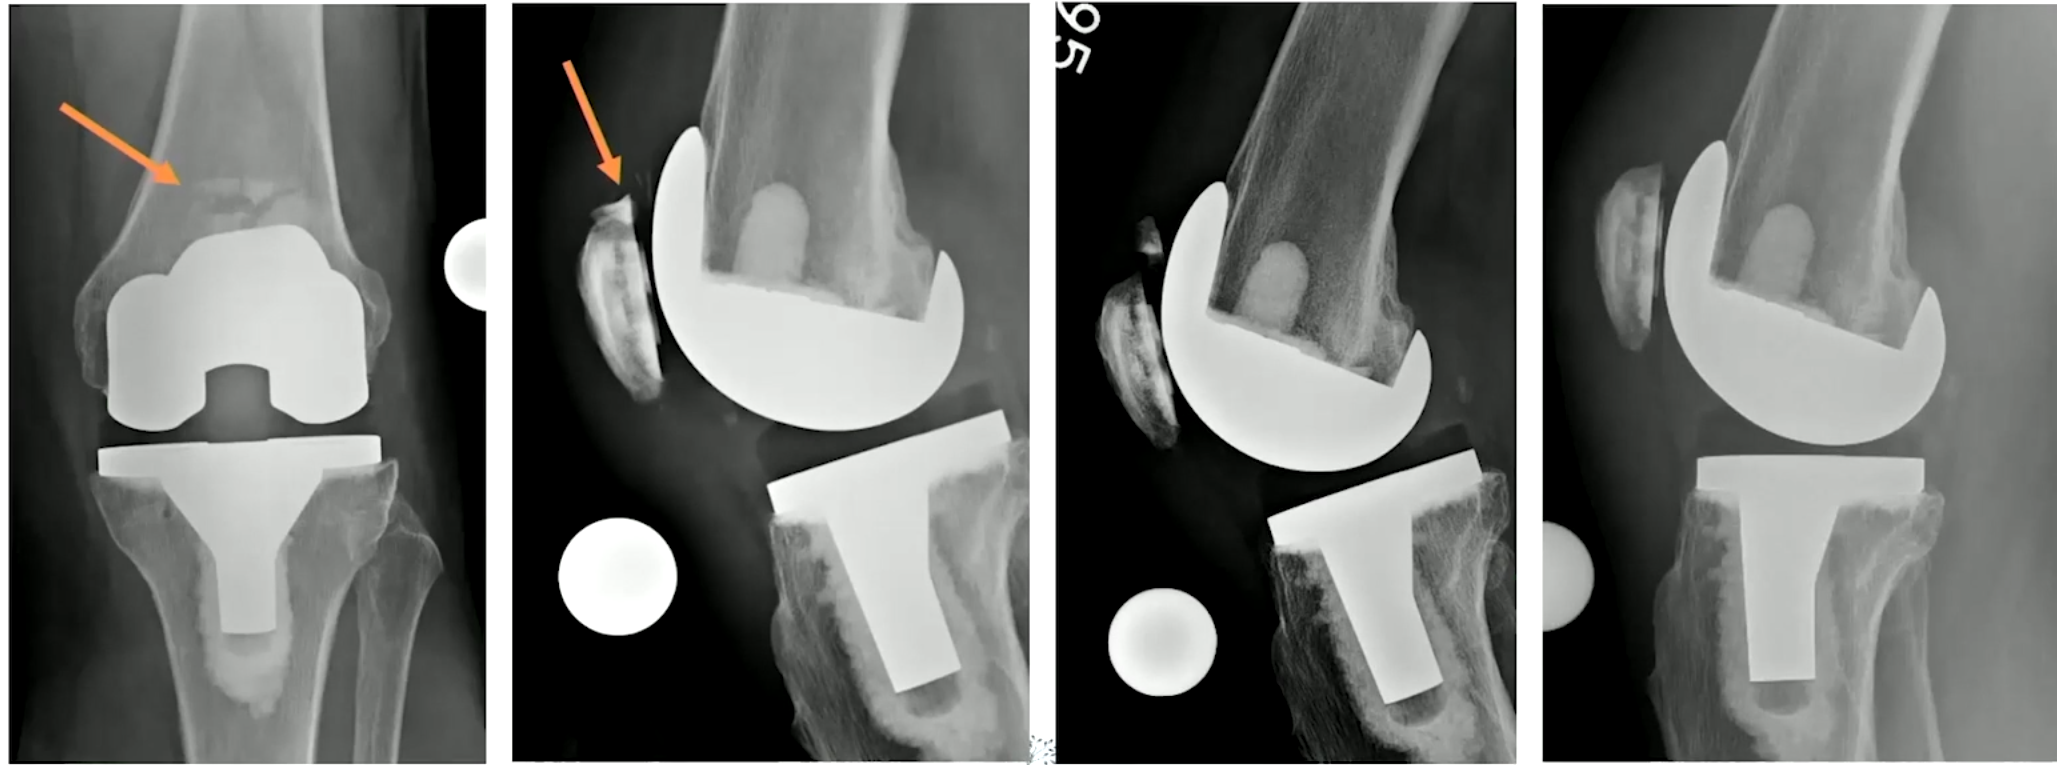

Type I, II, III 로 나뉠 수 있는데 모두 intact한 경우 I, implant는 intact하나 extensor mechanism이 작동하지 않을 때는 II, implant도 loosening 되고, implant 도 풀린 경우에는 III 로 나뉠 수 있습니다.

중요한 것은 Type II 인데, 폄근의 기능을 상실하였기 때문에 수술적인 치료가 필요합니다. 안에 들어간 implant는 정상일 수도 있으며, Bone Stock 이 남아있는 정도를 확인하여 수술의 종류를 설정할 수 있습니다. (대게 고령에 뼈 상태가 좋을 수 없으니 Partial patellectomy를 가장 많이 할 것 같습니다.)

아래와 같은 방식으로 여러가지 수술을 시행해 볼 수 있습니다. (ORIF, 뼈와 근육을 연결한 부위를 채취하여 기존의 patella 부분과 tibia 부분을 연결하도록 꼬매서 폄근육을 재건하는 경우, Suture anchor를 이용해서 repair 하는 경우, K-wire를 이용한 tension band wiring을 시행해 볼 수 있습니다.)

Type III의 경우 골질의 양에 따라 두개로 선택지를 나누어 치료를 할 수 있습니다.